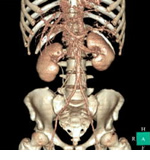

さらに進んで、3D処理をするとこのようにみえます。

腎臓や腹部大動脈がよく見えますね。